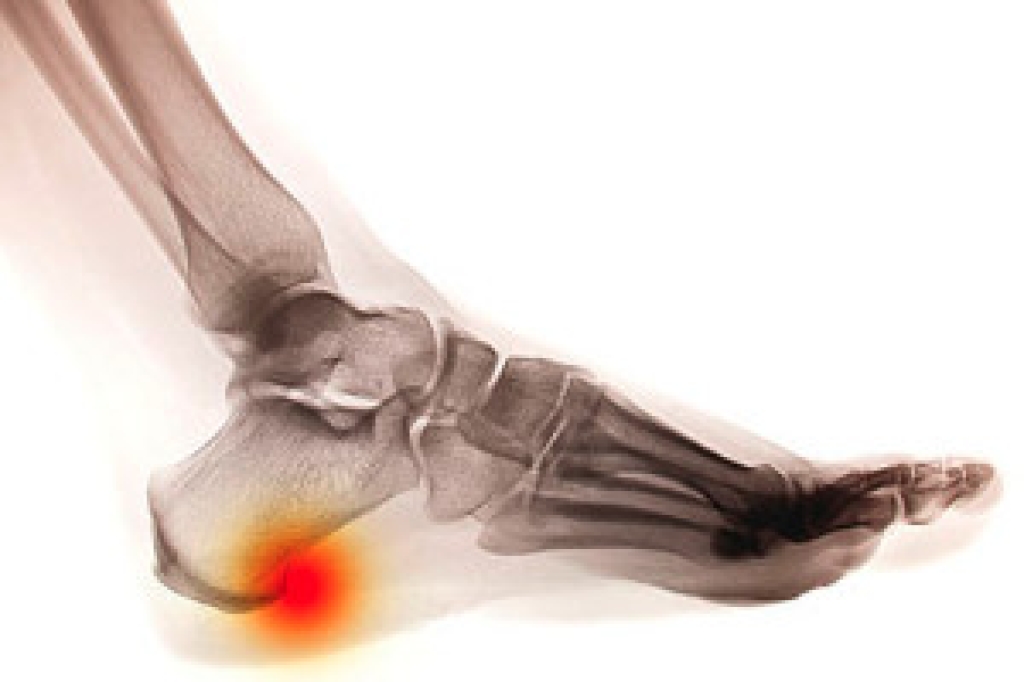

A heel spur is a bony growth that forms on the heel of the foot. It consists of a calcium deposit which forms under the heel bone. This condition often produces severe pain and discomfort, and may become worse while putting pressure on the heel. Many patients find mild relief by wearing shoe inserts, as this may be beneficial in reducing impact on the heel. Additionally, it can help to wear shoes that have excess cushioning in the heel area, because this can aid in minimizing inflammation. A proper diagnosis is generally achieved by performing an X-ray of the foot, which can determine the size and location of the heel spur. If you have developed a heel spur, it is advised that you speak to a podiatrist so proper treatment can begin.

Heel spurs are formed by calcium deposits on the back of the foot where the heel is. This can also be caused by small fragments of bone breaking off one section of the foot, attaching onto the back of the foot. Heel spurs can also be bone growth on the back of the foot and may grow in the direction of the arch of the foot.

The pain associated with spurs is often because of weight placed on the feet. When someone is walking, their entire weight is concentrated on the feet. Bone spurs then have the tendency to affect other bones and tissues around the foot. As the pain continues, the feet will become tender and sensitive over time.